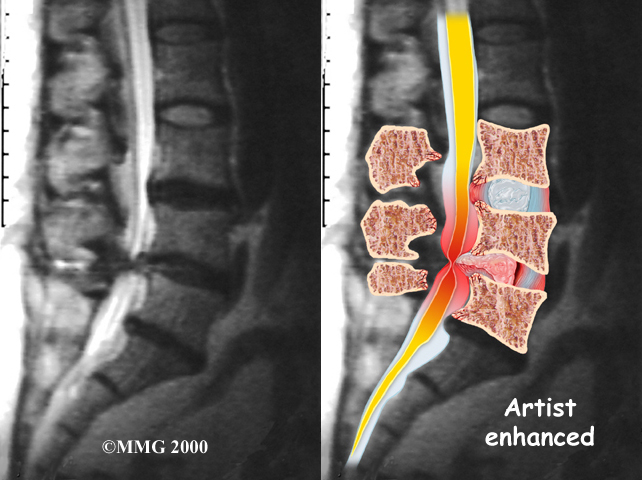

The best way to see the effects and extent of lumbar spinal stenosis is with a magnetic resonance imaging (MRI) scan. The MRI machine uses magnetic waves rather than X-rays to show the soft tissues of the body. This test gives a clear picture of the spinal canal and whether the nerves inside are being squeezed. This machine creates pictures that look like slices of the area your doctor is interested in. The test does not require dye or a needle.

Computed tomography (a CT scan) may be ordered for those patients who can’t have an MRI for some reason, when the results of the MRI are unclear, or symptoms don’t match the MRI findings. The CT scan is a detailed X-ray that lets your doctor see slices of bone tissue. The image can show any bone spurs that may be sticking into the spinal column and taking up space around the spinal nerves.